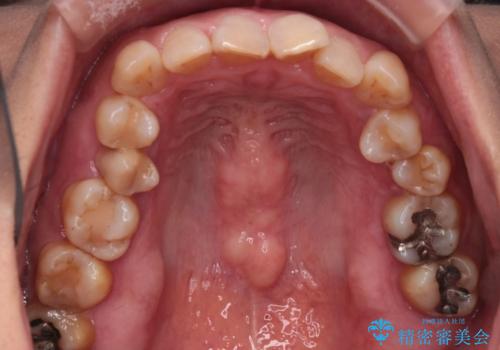

インビザラインで非抜歯矯正|ゴムかけで下顎犬歯の低位を改善し、噛み合わせも最適化

- 患者様は、下顎の犬歯が通常より低い位置にあり、噛み合わせのバランスが崩れていることを気にされて来院されました。診査の結果、抜歯せずに歯をきれいに並べるスペースを確保しながら、**ゴムかけ(顎間ゴム)**を使用して下顎犬歯の高さを適正に調整する方針を立てました。併せて、奥歯の噛み合わせも改善し、全体のバランスを整えることを目標としました。

治療はインビザライン(マウスピース矯正)を使用し、歯列全体を計画的に移動させながら、下顎犬歯の低位をゴムかけによって徐々に引き上げました。患者様にはゴムの装着をしっかり継続していただき、順調に改善が進行。最終的に奥歯の噛み合わせも安定し、全体の咬合バランスが整いました。治療後は「自然な噛み心地になり、見た目も満足」と患者様にも喜んでいただきました。